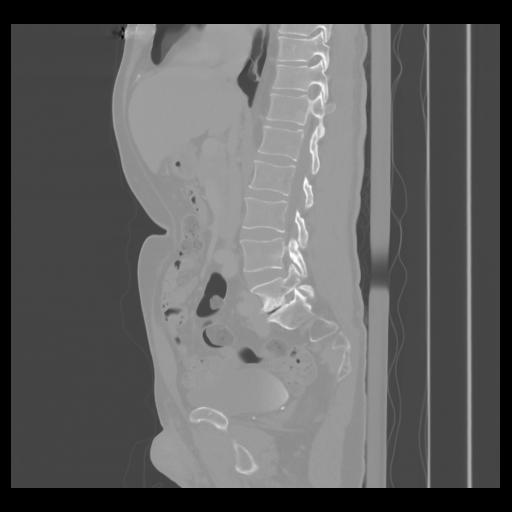

36 CUERPO,CE,Sagittal,3.000,CUERPO,Sagittal,